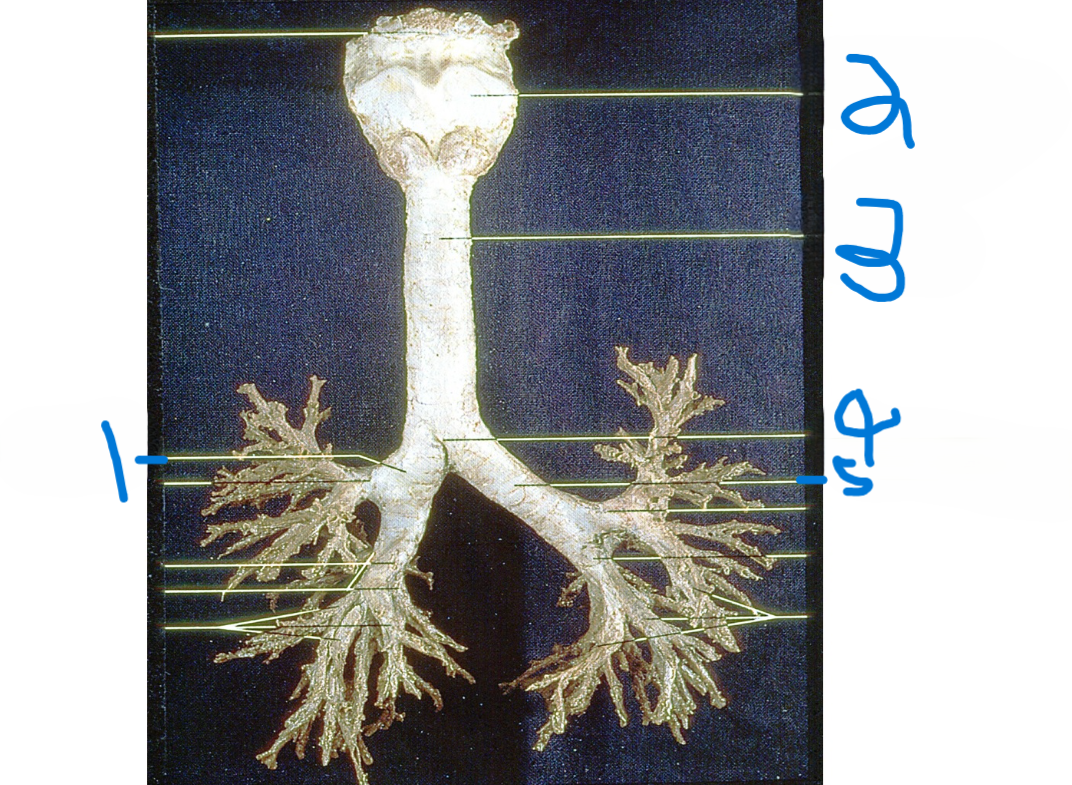

Right main bronchus

What is depicted by #1

Thyroid cartilage

What is depicted by #2

Trachea

What is depicted by #3

Carina

What is depicted by #4

Left main bronchus

What is depicted by #5